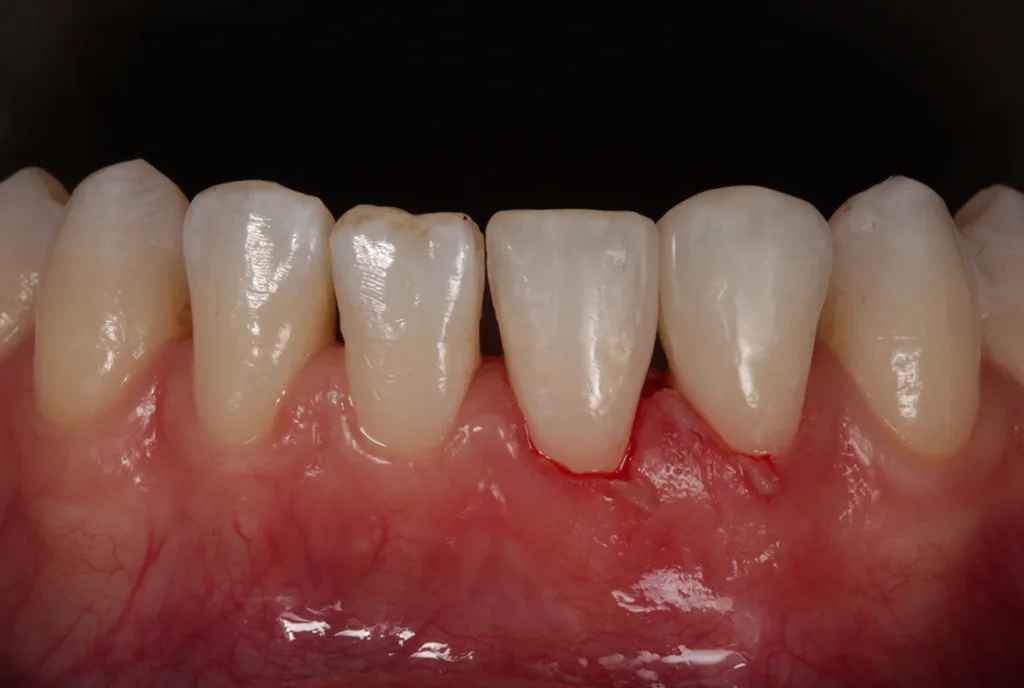

Die Zahnproportionen 31/32 erscheinen nach Aufbau mit Komposit insbesondere im mesiodistalen Bereich etwas „ausgeprägter“ im Vergleich zur kontralateralen Seite und sollten daher als Kompromiss betrachtet werden. Die leicht eingekerbten/gezackten Inzisalkanten wünschte sich die Patientin etwas geradliniger.

Dies hätte durch eine Formanpassung in Komposit bei 41 und 42 mit einem zusätzlichen Aufwand korrigiert werden können, wurde jedoch von der Patientin abgelehnt [5]. Für sie ist das Ergebnis sehr zufriedenstellend. Für den Behandler stellt sich die Behandlung – als Kompromiss – ebenso als Erfolg dar.

Es zeigen sich postoperativ leichte Irritationen der Gingiva, die durch das Legen der Retraktionsfäden/Ligaturen entstanden sind und sich nach Abheilung und Reifung im Interdentalbereich noch adäquat ausformen werden, um somit einem ansprechenden dentogingivalen Erscheinungsbild zu entsprechen.

Die Zahnform der beiden unteren Schneidezähne 31 und 32 entspricht nach Diastemaschluss nun den Wünschen der Patientin (Abb. 10).